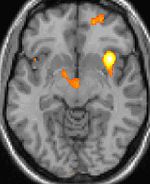

Positron emission tomography functional imaging shows activation of specific brain areas during a cluster headache.